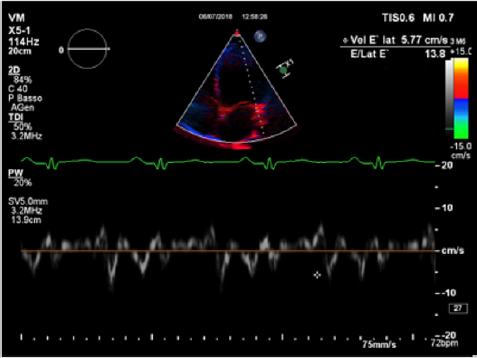

Physical examination showed a muscular man, the apex beat was not evident, the jugular at baseline showed an absent X’ descent with a positive hepato-jugular reflux and heart sounds were regular at the auscultation ; there was also minimal ankle swelling and , bilateral basal crackling rattles were audible at lung auscultation. The ECG showed a sinus rhythm with a frequency of 88 bpm, signs of left atrial enlargement, a left axial deviation and negative T-waves on D1 and aVL and from V4 to V6; no previous recent ECG was available for comparison. Chest X-ray showed pulmonary edema and an acute bronchopneumonia focus. Transthoracic echocardiography (TTE) revealed a dilated cardiomyopathy with severe left ventricular systolic dysfunction (LVEF 23% calculated with the Simpson biplane method) and dilatation (telediastolic diameter 79 mm) with moderate uniform hypertrophy (Figure 1a & 1b). There was grade II diastolic dysfunction (E/A waves ratio 1,9; E wave deceleration time 144 msec), “B-bump” on M-mode examination at the mitral valve level and an average E/e’ at tissue doppler analysis at the upper limit of the “grey zone”: 14 (Figure 2a-2d); global longitudinal peak systolic strain (GLPSS) was -7,4%; the left atrium was dilated; the right ventricle was dilated, slightly hypocontractile (tricuspidal annular plane systolic excursion, TAPSE, 16 mm) with a dilated right atrium; the inferior cava vein showed a normal dimension and collapsibility.

Figure 2c: An average E/e’ ratio at TDI analysis at basal septal and lateral level of 14 (grey zone).